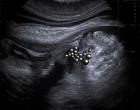

A monitoron szürke foltok és formák jelentek meg, amelyeket én képtelen voltam értelmezni. A vizsgálatot végző orvos homloka apránként ráncolódott, mintha valamit keresne, amit nem szeretne megtalálni.

Az ultrahangon idegen tárgyak árnyékai jelentek meg Lili belében. A magyarázat, amit kaptam, még mindig kusza volt a fejemben: valamilyen apró, erős mágnesek kerültek be a testébe. Összetapadva szorították közre a bélszakaszt, és ha nem avatkoznak be időben, súlyos szövődmények is lehettek volna. A gondolat is kirázott, hogy hosszú órákon át abban a hitben ringattam magam, hogy mindez csak egy múló hasfájás.

– Szeretnék mindent világosan elmondani – kezdte. – Amit az ultrahangon láttunk, az valóban néhány apró mágnes. Ha így együtt kerülnek be, össze tudják szorítani a bélszakaszt. Ezt most műtéti úton kell eltávolítanunk.